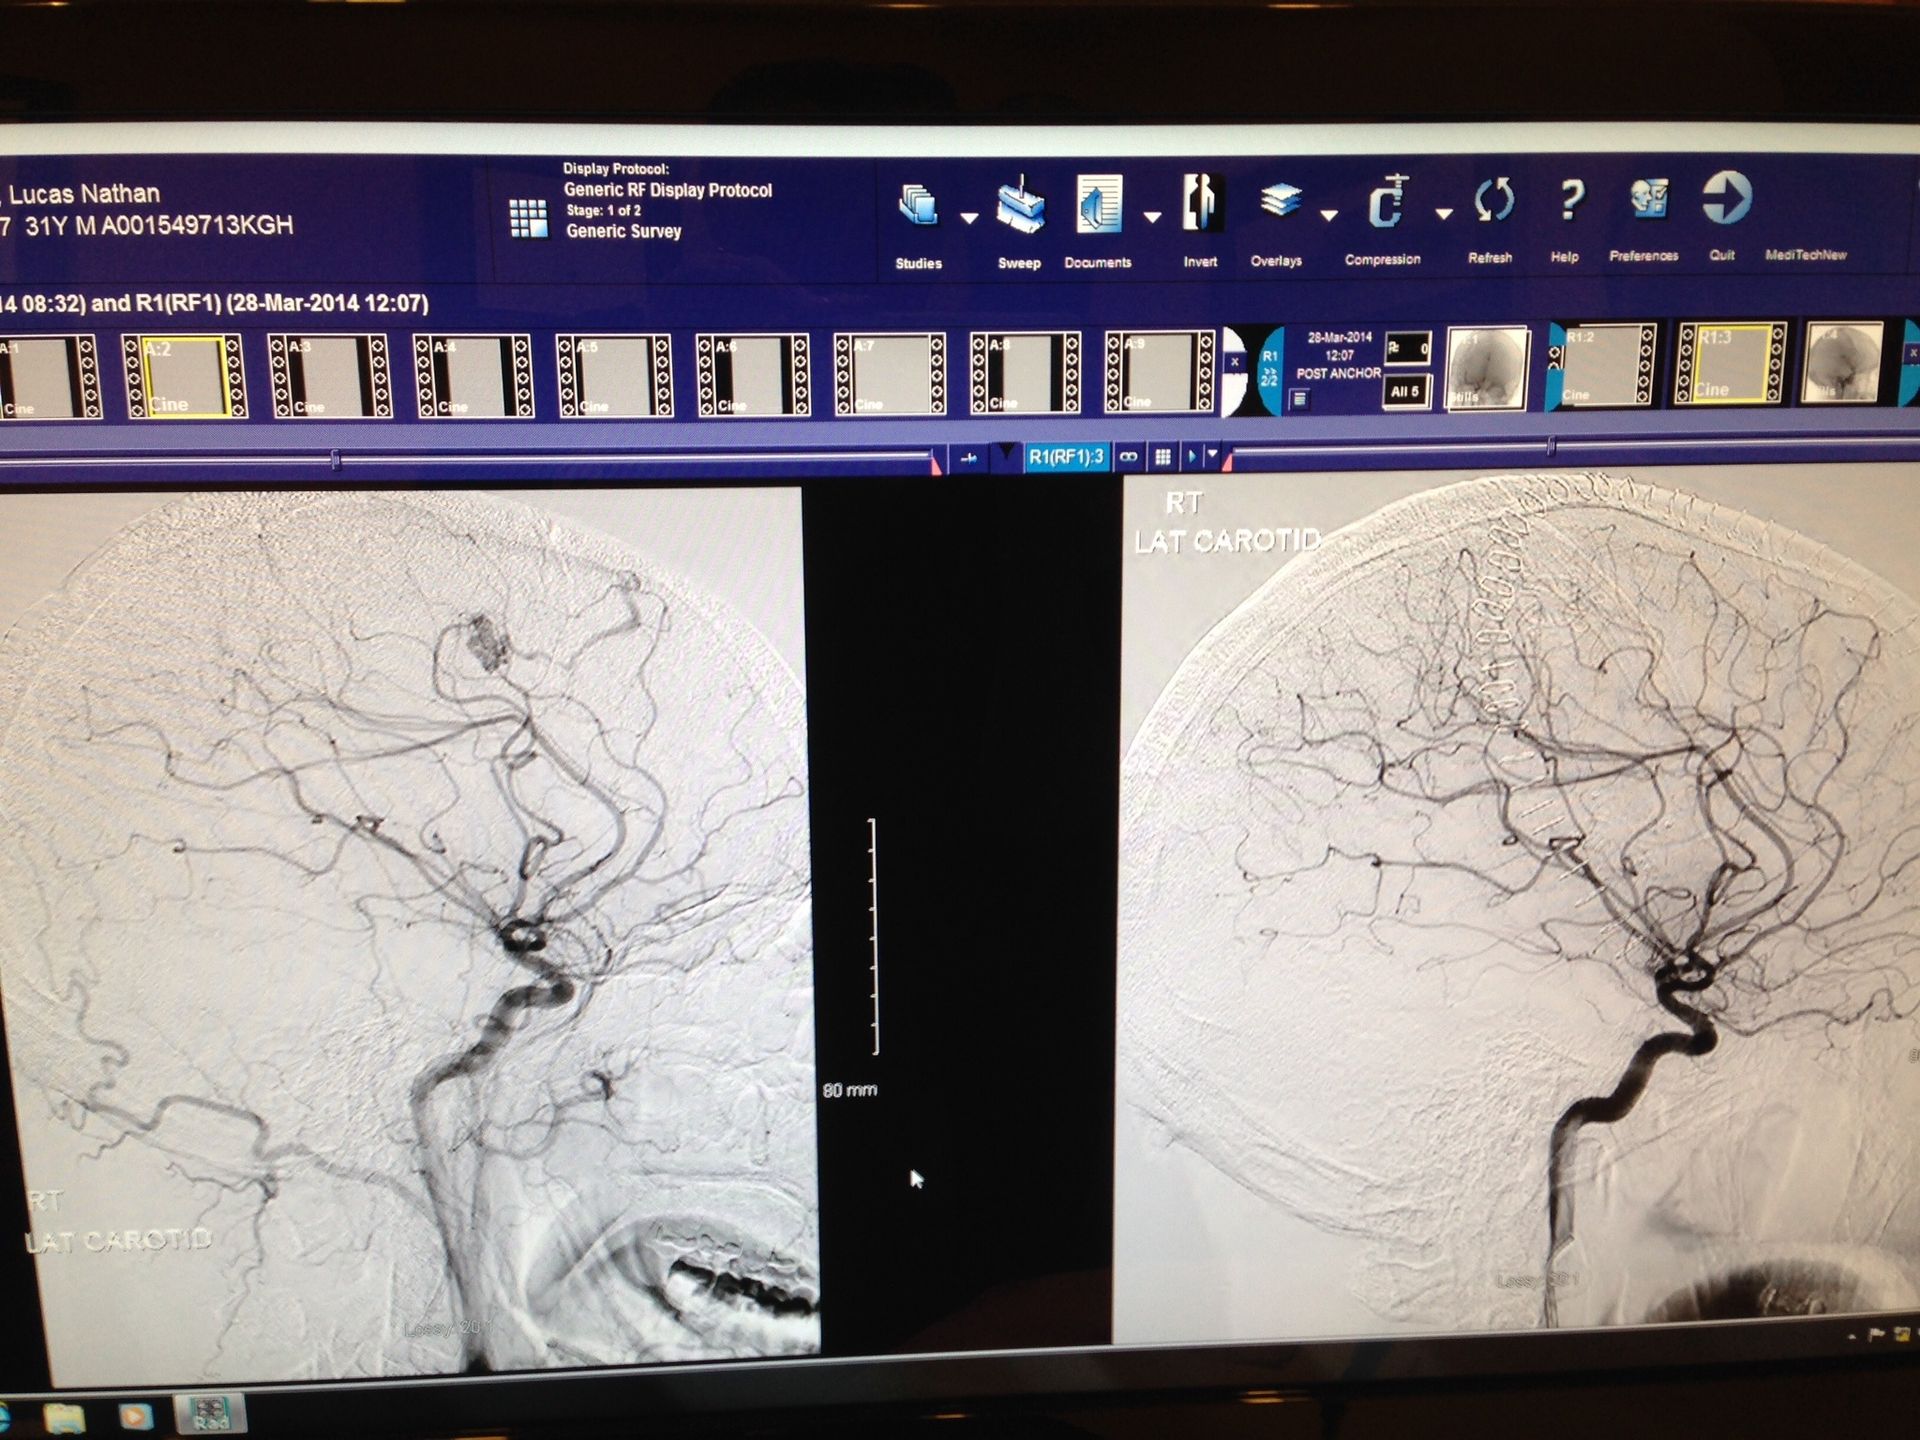

More than a decade ago, my life changed after an arteriovenous malformation (AVM) ruptured in my right frontal lobe causing a sever hemorrhagic stroke. What followed has been a long and complicated recovery that affected every part of my life. My body, my relationships, my work, my sense of identity, and my role within my family all shifted at once.

Lucas Jackson knows TBI recovery from the inside. In 2014, a ruptured AVM led to a massive stroke that destroyed two-thirds of his right frontal lobe. He had to relearn how to walk, talk, and function, while raising two young kids and navigating a marriage that eventually became another casualty of trauma.